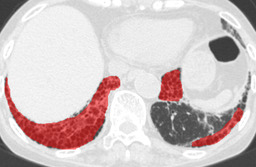

In this paper, we define partial annotation as an annotation format in which only one class is chosen for the annotation and only pixels belonging to the chosen class are annotated per image. For example, in Figure 1(a), although there is ground glass opacity in the image, only consolidation is chosen for annotation and pixels of consolidation are annotated. Partially annotated dataset is less informative for training, however, it is much easier to create compared to fully annotated dataset since annotators only need to focus on one class at a time during the annotation task.

Statistics of our dataset are shown in Table 1 and typical images and their annotations for each DLD pattern are shown in Figure 1. In our partially annotated dataset, all the pixels in a slice were manually classified into two classes: dominating DLD pattern and other tissues. In other words, all the pixels in our dataset were assigned one of the labels from either of the two label sets, Lstrong={lCON,lGGO,lHCM,lEMP,lNOR}subscript𝐿𝑠𝑡𝑟𝑜𝑛𝑔subscript𝑙𝐶𝑂𝑁subscript𝑙𝐺𝐺𝑂subscript𝑙𝐻𝐶𝑀subscript𝑙𝐸𝑀𝑃subscript𝑙𝑁𝑂𝑅L_{strong}=\{l_{CON},l_{GGO},l_{HCM},l_{EMP},l_{NOR}\} or Lweak={lCON¯,lGGO¯,lHCM¯,lEMP¯,lNOR¯}subscript𝐿𝑤𝑒𝑎𝑘subscript𝑙¯𝐶𝑂𝑁subscript𝑙¯𝐺𝐺𝑂subscript𝑙¯𝐻𝐶𝑀subscript𝑙¯𝐸𝑀𝑃subscript𝑙¯𝑁𝑂𝑅L_{weak}=\{l_{\overline{CON}},l_{\overline{GGO}},l_{\overline{HCM}},l_{\overline{EMP}},l_{\overline{NOR}}\}. For example, in Figure 1(a), colored pixels were labeled as lCONsubscript𝑙𝐶𝑂𝑁l_{CON} and all the other pixels were labeled as lCON¯subscript𝑙¯𝐶𝑂𝑁l_{\overline{CON}}. In this paper, we call pixels of label lLweak𝑙subscript𝐿𝑤𝑒𝑎𝑘l\in L_{weak} and lLstrong𝑙subscript𝐿𝑠𝑡𝑟𝑜𝑛𝑔l\in L_{strong} as weakly annotated pixels and strongly annotated pixels respectively. Our pixel-wise annotations were created in the following steps. First, up to 3 slices were chosen for the annotation for each HRCT scan and for each slice, one representing DLD pattern was chosen by a radiologist. Second, three radiologists performed pixel-wise binary annotation (e.g. binary annotation between lCONsubscript𝑙𝐶𝑂𝑁l_{CON} or lCON¯subscript𝑙¯𝐶𝑂𝑁l_{\overline{CON}}) for each slice. Finally, the radiologists’ annotations were merged by taking majority classes for each pixel (i.e. pixels labeled as a DLD pattern by more than 2 radiologists became the corresponding DLD pixel). In addition to the DLDs annotation, lung fields were manually segmented under the supervision of radiologists and training and testing were conducted only within the lung fields.

Figure 1: Typical slices for each DLD classes. Slices of HRCT are shown in lung window setting (window-center=-600, window-width=1500) with annotated labels superimposed in transparent colors. Note that even if more than one DLD patterns existed, only one DLD pattern was chosen and annotated for a slice to facilitate the annotation process.